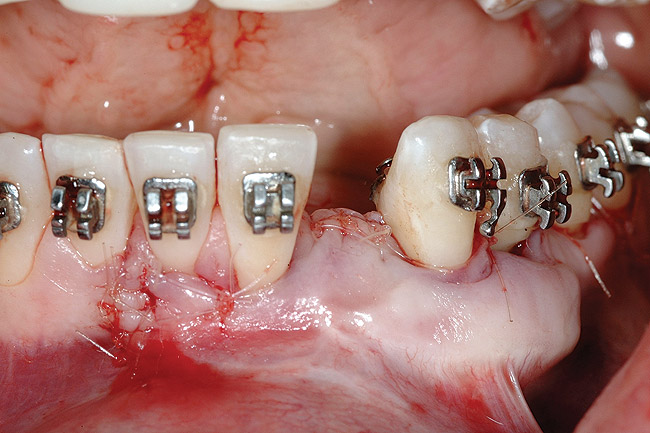

Figure 9  Orthodontic distraction osteogenesis to develop the implant site of tooth No. 23.

Figure 9

Following the first goal of orthodontia—moving tooth No. 22 to a proper functional and anatomical position—a periodontal reevaluation was performed, demonstrating an improvement in short- and long-term tooth prognosis. At this time, the decision was made to abort continual extrusion of teeth Nos. 21 and 22, although some attachment level discrepancy remained between Nos. 21 and 22 (Figure 14). Implant diagnostics ensued and included mounted study models and a diagnostic wax-up. A scanning appliance was created to demonstrate the desired prosthetic outcome requirements, and the patient was referred for computed tomography (CT) scans. CT scan assessment demonstrated successful orthodontically directed GBR to allow implant placement (Figure 15 through Figure 16). Only minor GBR therapy would be needed and could be accomplished simultaneously with implant installation. Guided implant placement occurred, using an open flap approach (Figure 17). During surgery, root dehiscences were noted on teeth Nos. 21, 22, 24, and 25, as well as the anticipated dehiscence following implant placement at No. 23 (Figure 18). A positioning reference (index) was secured after implant placement to facilitate a provisional prosthesis at stage II surgery. Cortical perforations then were placed adjacent to the implant to encourage angiogenesis (Figure 18), and mineralized freeze-dried bone allograft enhanced with platelet-derived growth factor was placed over the dehiscences for purposes of guided tissue regeneration and GPR (Figure 19). A highly resorbable collagen membrane was placed to stabilize the allograft. The flap was coronally repositioned, and primary-intention wound healing was achieved (Figure 20 and Figure 21). Following 4 months of stage I surgery, implant uncovery and immediate provisionalization was performed in conjunction with connective tissue grafting. Final orthodontic tooth movement then ensued, using the implant as anchorage to optimize end-tooth movements, interroot separation, and the cuspid-protected occlusal scheme. A final impression then was secured, and a zirconia abutment (Figure 22) with an all-ceramic restoration was fabricated for the prosthetic phase completion of No. 23 (Figure 23] through Figure 25).